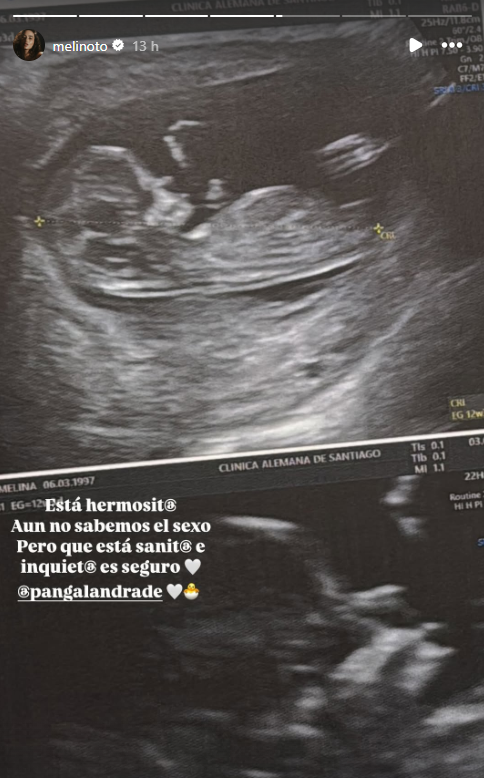

Este jueves, Melina Noto enterneció las redes sociales tras compartir por primera vez una ecografía de su embarazo tras asistir a una consulta médica con su pareja y padre de su futuro hijo o hija, Pangal Andrade.

Luego de unos minutos, Noto subió la fotografía de la ecografía Doppler, donde se visualiza al bebé en gestación.

“Está hermosit@. Aún no sabemos el sexo, pero está sanit@ e inquiet@ es seguro“, indicó Melina en la publicación.

Revisa la foto acá: